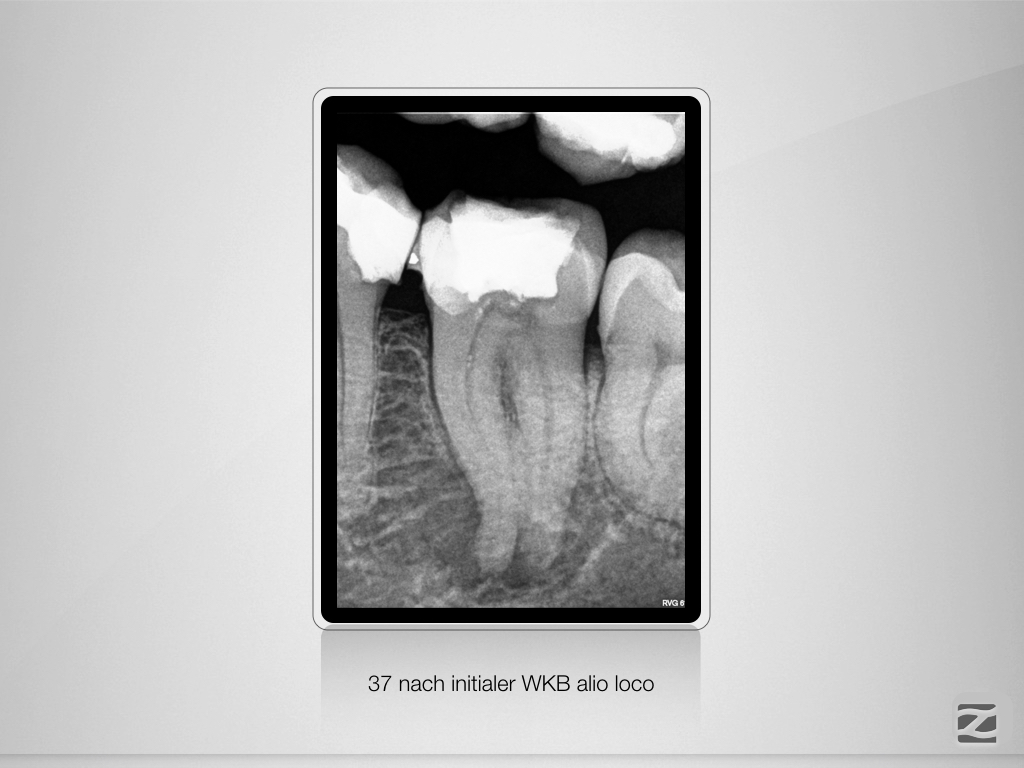

37D.001

Geometrische Herausforderung